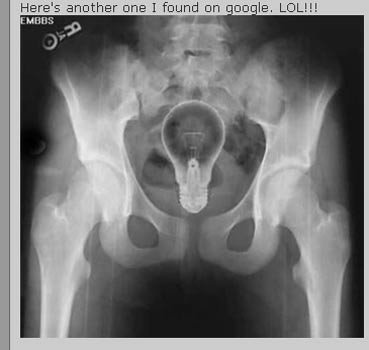

Trong trường hợp này th́ sáng kiến nhét bóng đèn vào người lại là một tối kiến.